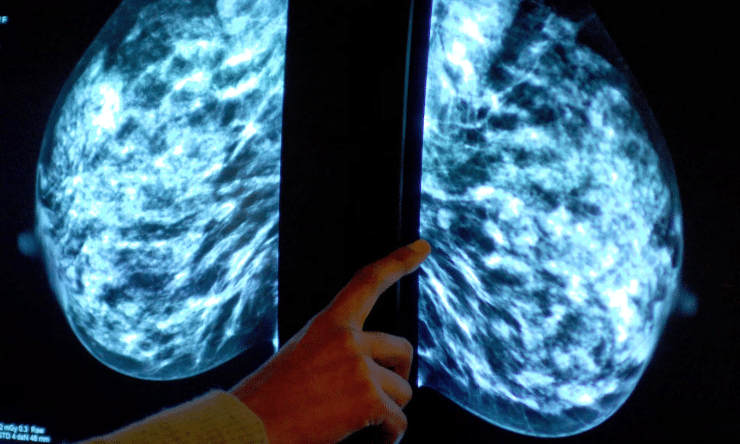

Now, a new AI model is changing the game. Trained using thousands of mammogram images, this AI system can identify subtle patterns and signs of cancer that might be too faint or complex for the human eye to catch.

A study conducted at Northwestern University showed that the AI tool performed with remarkable accuracy. It not only detected cancers that radiologists missed but also reduced the number of false positives, meaning fewer patients are subjected to unnecessary biopsies or further tests.